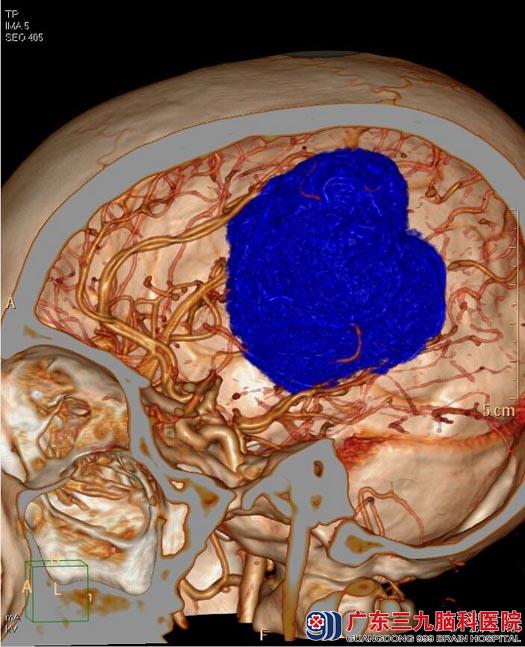

头颅MR检查提示:松果体上方正中大脑镰两旁占位性病变,大小约为7.9cm×6.5cm×6.2cm;邻近脑组织受压移位,考虑脑膜瘤可能性大。头颅CTA提示:松果体上方正中巨大软组织肿块,强化明显,其内较多迂曲血管分布,周缘较多血管缠绕,邻近双侧大脑前动脉、大脑大静脉及分支受压明显移位,邻近直窦前部及下矢状窦部分包绕。

▲头颅CTA